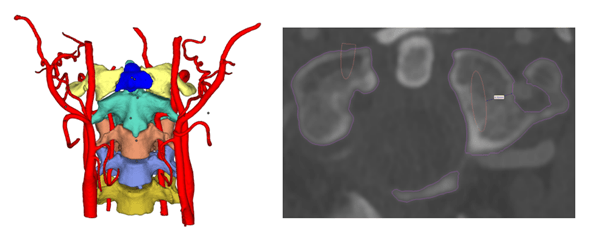

3D bioprinting, or 3D bioprinting, is an additive manufacturing process in which organic or biological materials, such as living cells and nutrients, are combined to create natural three-dimensional structures that resemble tissue. In other words, bioprinting is a type of 3D printing that can produce anything from bone tissue to blood vessels to living tissue. It is used in various medical research and applications, including tissue engineering, drug testing and development, and innovative regenerative medicine therapies. The very definition of 3D bioprinting is still evolving. Essentially, 3D bioprinting works similar to FDM 3D printing and belongs to the material extrusions family. (Although extrusion is not the only bioprinting method)

3D bioprinting uses material (bio-ink) expelled from a needle to create printed layers. These materials, called bioinks, are mainly composed of living substances, such as cells in a carrier material – such as collagen, gelatin, hyaluronic acid, silk, alginate or nanocellulose, molecules that act as structural growth support and nutrients to provide support.